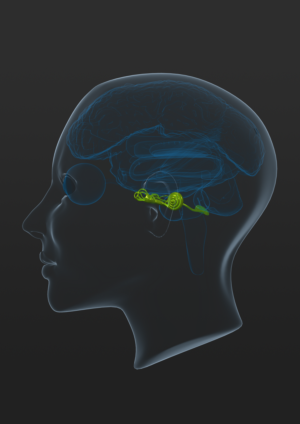

transparent 3D concussion booklet